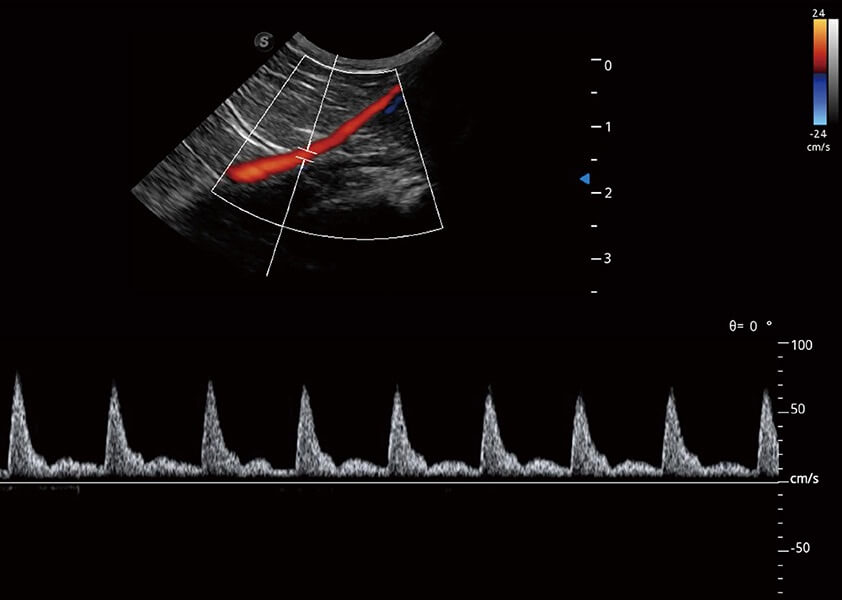

(猫)髂动脉血流频谱

(犬)肾脏血流